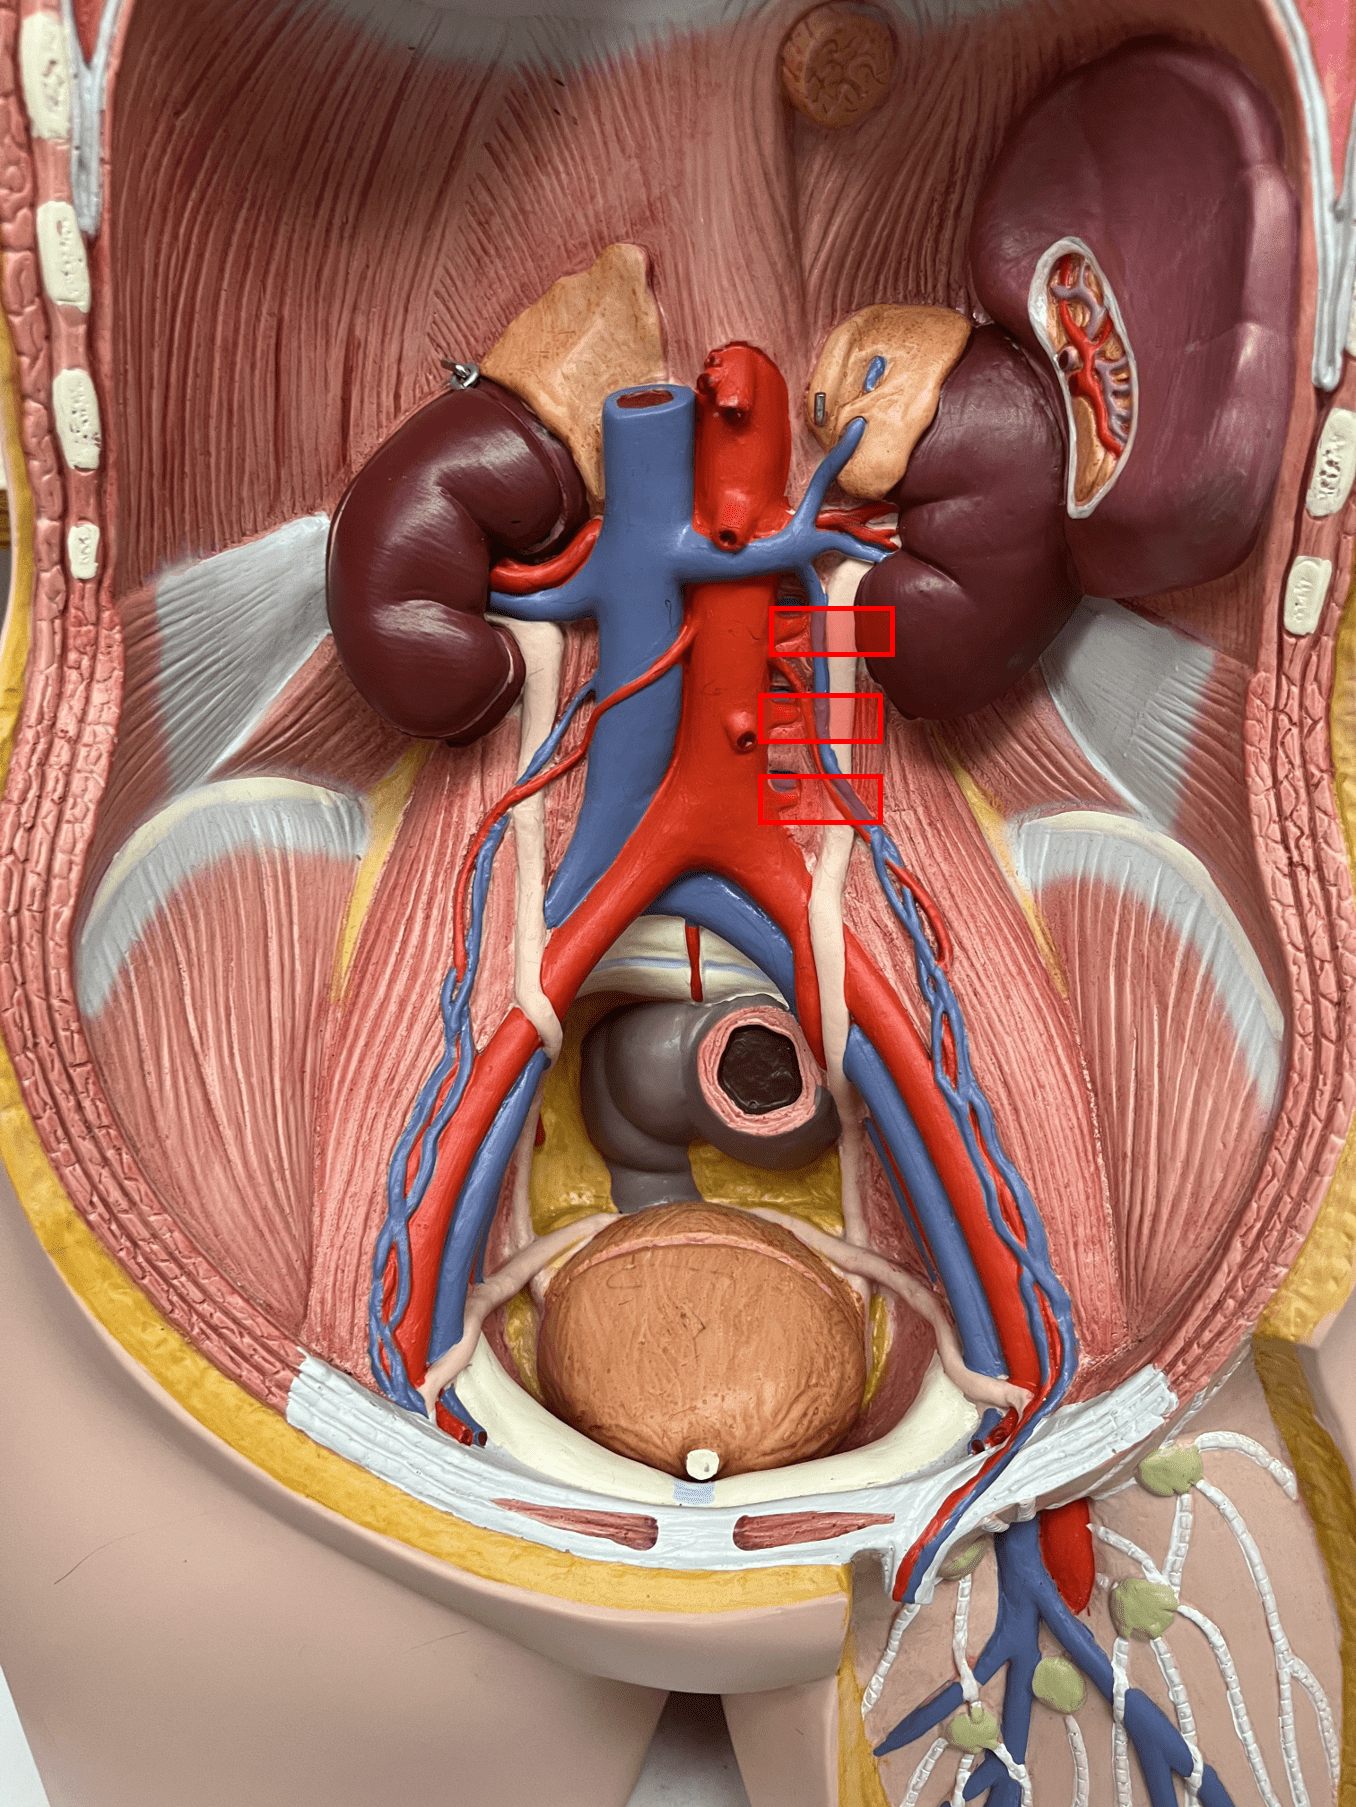

• Composed of loose connective tissue and collagen fibers.

• Also known as the tunica adventitia.

7

New cards

external elastic membrane

• A thin layer of elastic connective tissue.